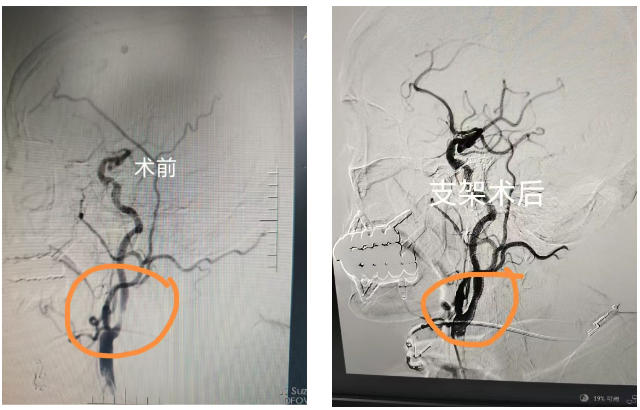

科室:神经内科